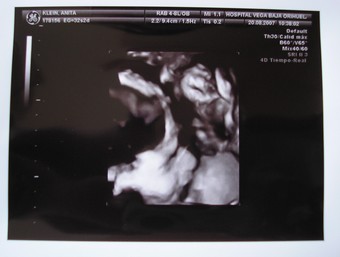

Pont nekem is az jutott eszembe,mint Móninak,hogy szinte csak most mutattad az első UH képet és már lassan szülsz...

Így elmegy 9 hónap

....